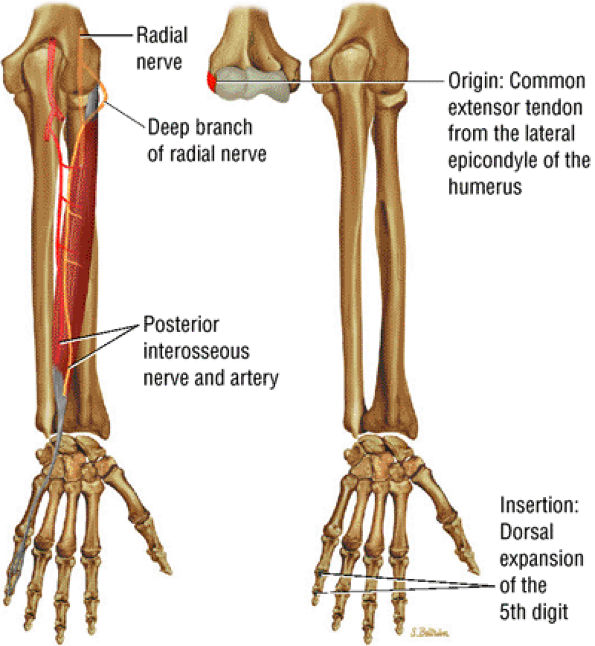

FIGURE 10.14 ● EXTENSOR DIGITI MINIMI The extensor digiti minimi extends the proximal phalanx of the little finger at the metacarpophalangeal joint and contributes to wrist extension. Because the extensor digiti minimi tendon lies just superficial to the radioulnar articulation, it is often the first tendon to be involved in rheumatoid arthritis.

|